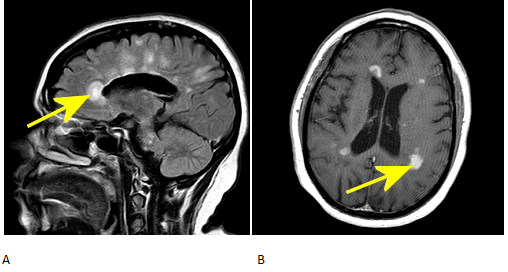

The McDonald Criteria for diagnosing MS was updated in 2010 to help simplify the use of images, and in cases, use one MRI to establish dissemination in space and time and allow for earlier diagnosis. In those criteria, the gold standard remains 2+ attacks = clinical evidence of 2+ lesions = 1 lesion + 1 episode by reliable history, but the presence of both gadolinium-enhancing and non-enhancing lesions on baseline MRI can substitute for a follow-up scan as long as the enhancing lesion is not due to a non-MS pathology. Gad-enhancing lesions in multiple sclerosis represent disease activity usually of up to 6 months; by contrast, T2 lesions represent older, scarred areas. See Figure 1.

Figure 1: A. Dawson’s fingers on sagittal FLAIR image. B. GAD-enhancing lesions on axial T1 image.